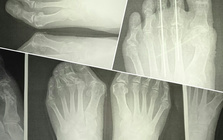

靴の健康被害、外反母趾。

外反母趾の問題は痛みだけではありません。

その変形症状から多くの身体の不具合と

ほかの症状、病気を発症させてしまう方、

外反母趾対策

Hallux valgus